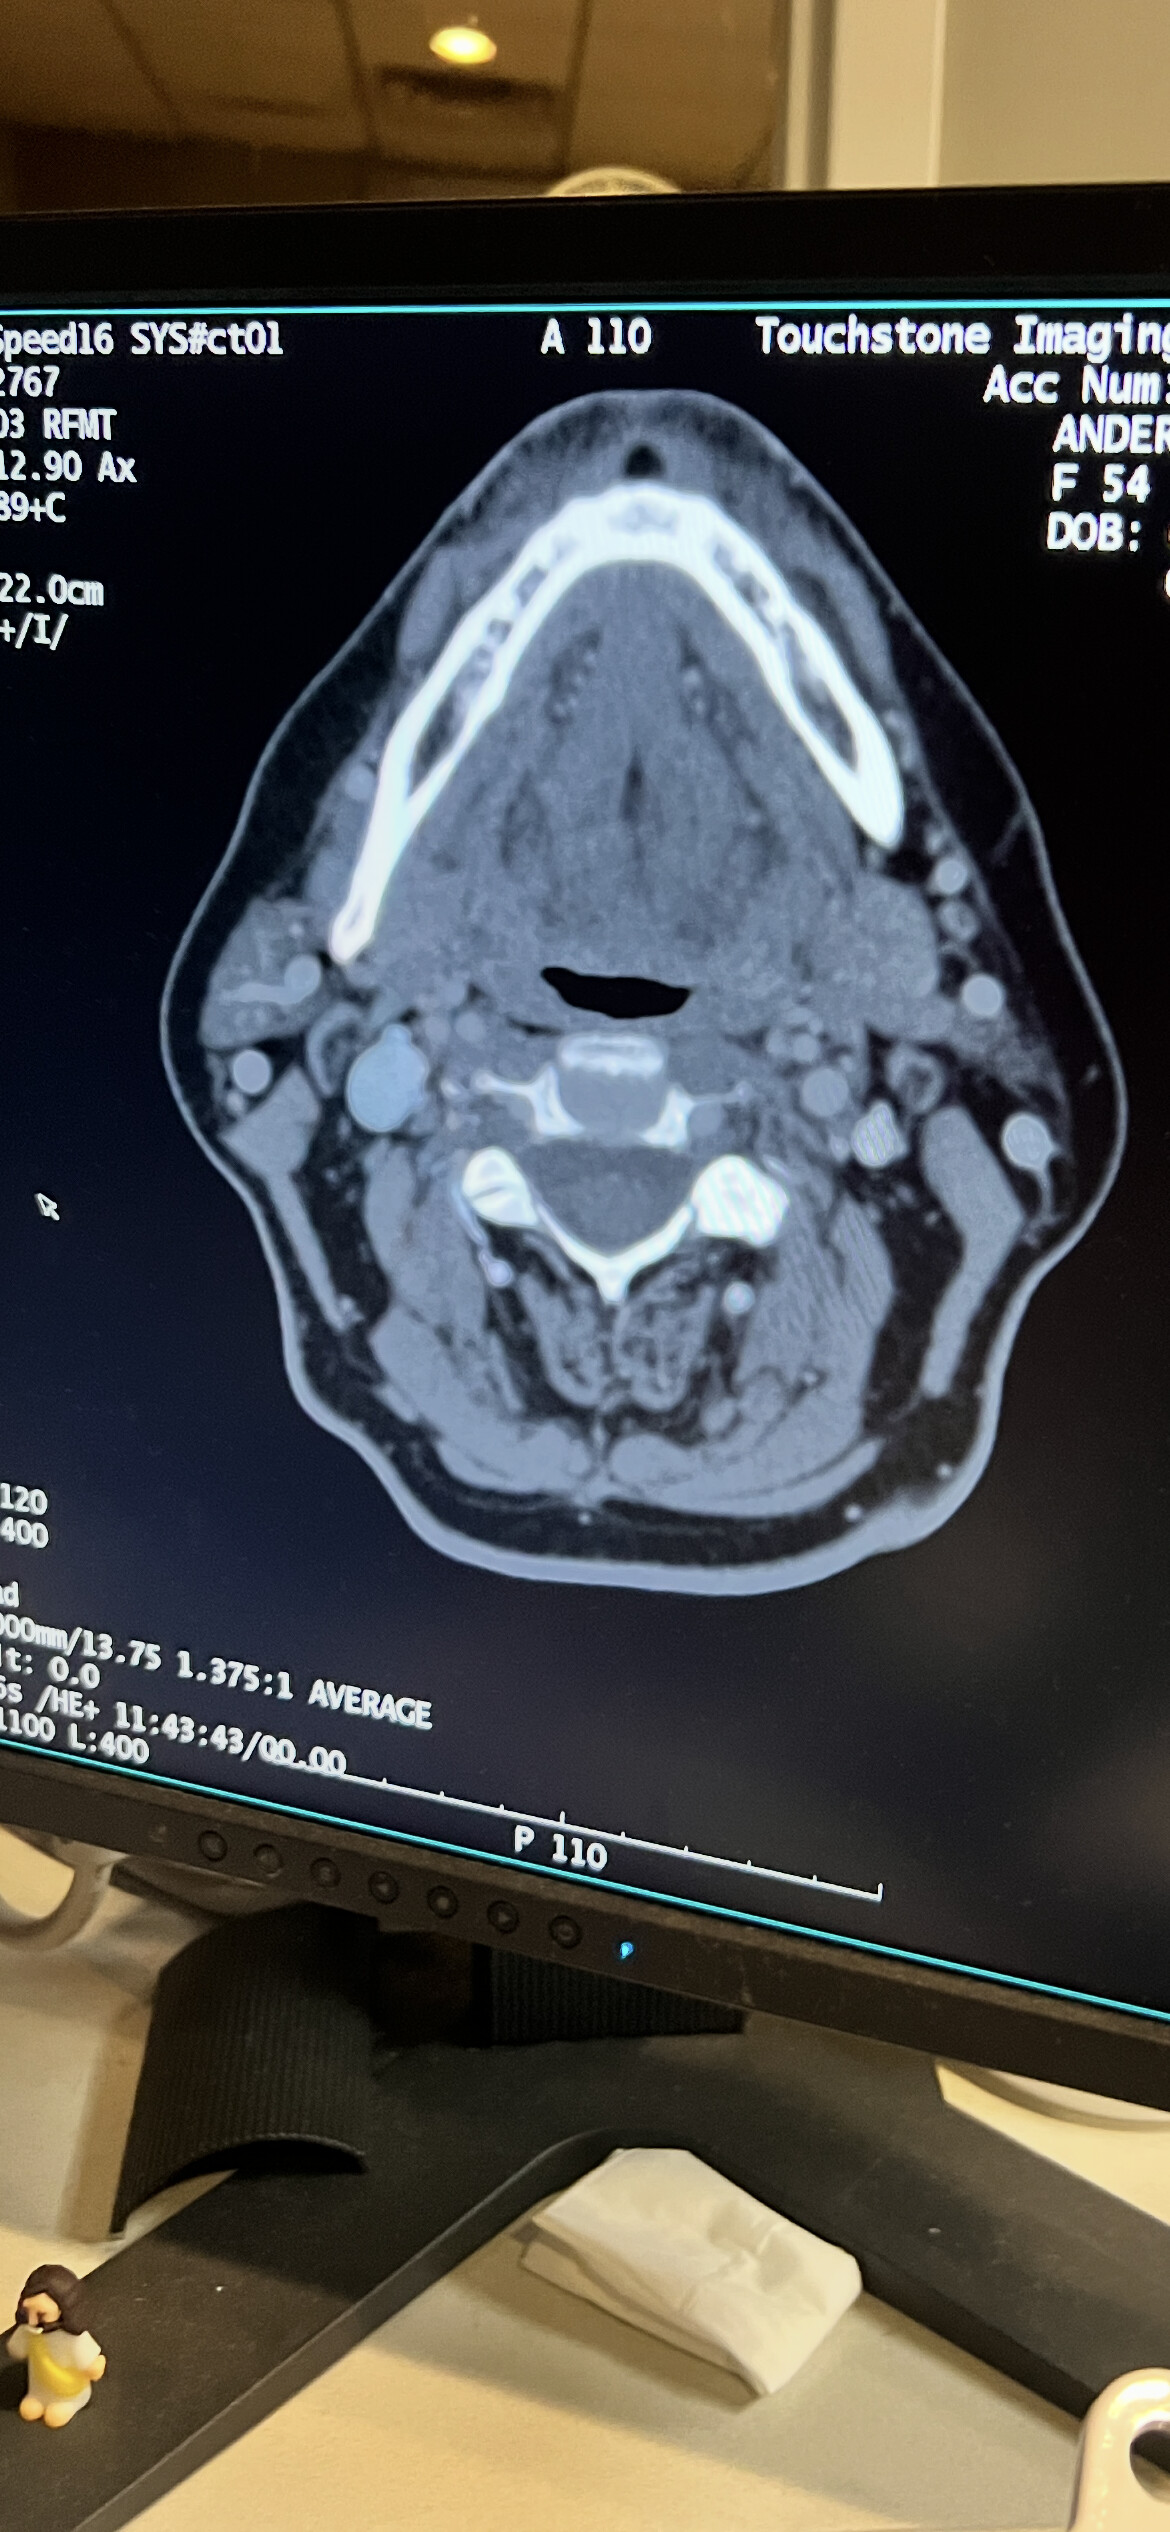

As she played it I just snapped pictures with my phone and I’m even kind of at an angle so I know it’s not a great shot- I also don’t know what tells the most so I’m just posting these to see if they say anything about whats going on

I’ll see tomorrow if I can download all of it based on y’all’s instructions… I know this picture isnt just like yours… But it’s just another one that I have so I thought I would put it out there.